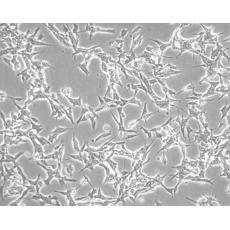

產品名稱 SK-N-BE(2)

中文名稱 人神經母細胞瘤細胞

組織來源 神經母細胞瘤;骨髓來源;男性

生長特性 mixed, adherent and suspension

形態特征 neuroblast

細胞描述 1972年11月從一們多次化療及放療的擴散性神經母細胞瘤患兒骨髓穿刺物中建立了SK-N-BE(2)神經母細胞瘤細胞株。 該細胞顯示中等水平的多巴胺-β-羥基酶活性。 有報道稱SK-N-BE(2)細胞的飽和濃度超過1x106細胞/平方厘米。細胞形態多樣,有的有長突觸,有的呈上皮細胞樣。 細胞會聚集,形成團塊并浮起